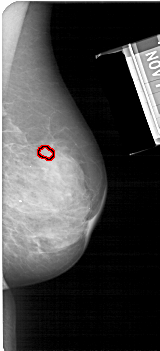

A_1683_1.RIGHT_CC

RIGHT_CC LINES 5281 PIXELS_PER_LINE 1966 BITS_PER_PIXEL 12 RESOLUTION 43.5 OVERLAY

FILE: A_1683_1.RIGHT_CC.OVERLAY

TOTAL_ABNORMALITIES 1

ABNORMALITY 1

LESION_TYPE MASS SHAPE OVAL MARGINS OBSCURED

ASSESSMENT 3

SUBTLETY 3

PATHOLOGY BENIGN

TOTAL_OUTLINES 1

BOUNDARY